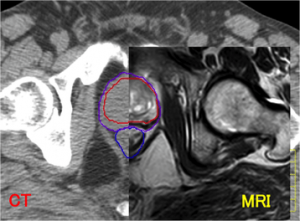

近年、放射線診断や放射線治療において、医用画像位置合わせは重要な技術になってきています。ここでは、医用画像解析に興味のある学生や研究者のために、医用画像位置合わせに必要な基礎知識についてまとめました。今回は、画像位置合わせに用いられる「画像の類似度の指標」を中心に紹介します。 2つの画像間で、片方の画像を移動、回転、変形させることにより、もう片方の画像に合わせこむ手法を画像位置合わせ(Registration)と言います。このRegistrationの技術は、医療現場において、様々なモダリティーから得られた画像の重ね合わせ(例えば、CT画像とMRI画像、MRI画像と PET画像など)に用いられ...